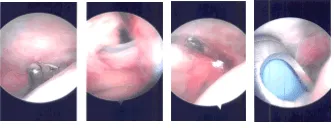

Se visualizaron las suturas. La sutura estaba anudada. Se logró una buena reparación. No había bursitis subacromial ni deshilachamiento. La junta del aire acondicionado tenía buena pinta. Se tomaron y guardaron las fotos finales.

Imágenes artroscópicas intraoperatorias

Se fijó al manguito rotador usando grapas de PLA x 5. La parte lateral del parche se fijó a la mayor tuberosidad usando grapas PEEK x 2. Se encontró en estado estable. Se tomaron y guardaron las fotos finales.